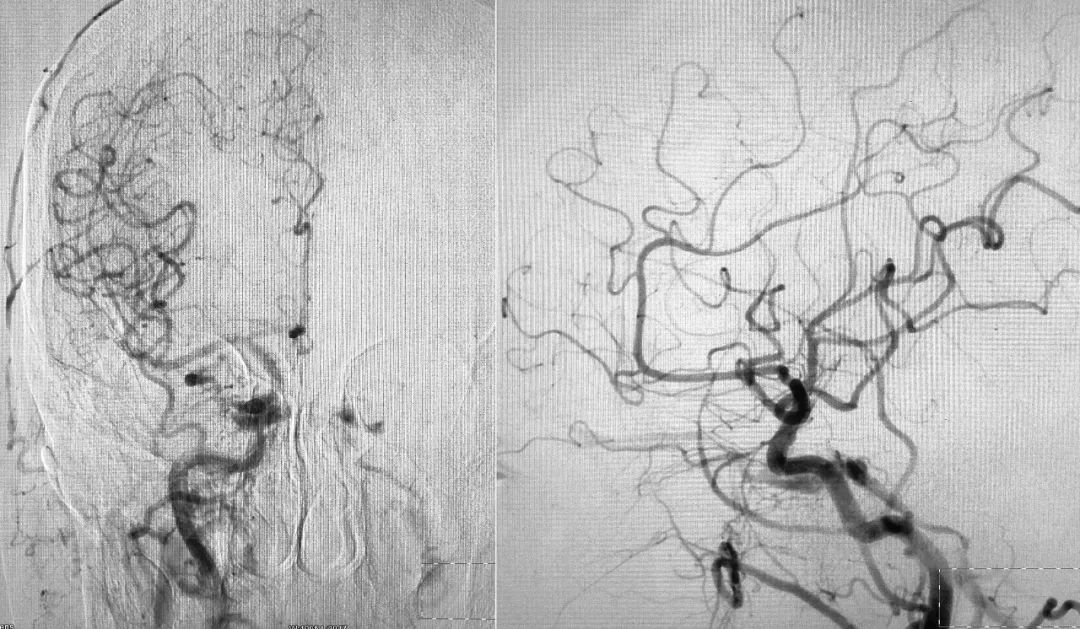

2018年10月12日行DSA示右侧海绵窦区硬脑膜动静脉瘘(Barrow D型),由双侧颈内、颈外动脉脑膜支供血,由右侧眼上静脉、岩下窦引流。

右侧颈总动脉正、侧位造影:

左侧颈总动脉正、侧位造影: